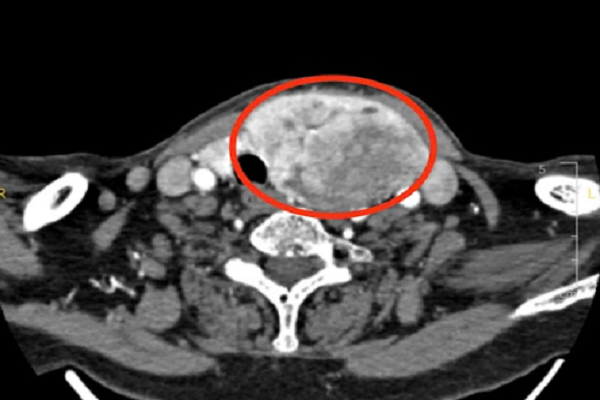

Kết quả chụp CT cho thấy, bà N.T.G (77 tuổi, ngụ tỉnh Tây Ninh) có khối bướu giáp đa nhân khổng lồ, trong đó thùy trái phát triển vượt mức với kích thước lên đến 9 cm, lộ hẳn ra ngoài, đè ép lên thực quản và chèn cả dây thần kinh thanh quản - Ảnh: BV

Kết quả khiến cả ê kíp không khỏi lo ngại. Bà mang một khối bướu giáp đa nhân khổng lồ, trong đó thùy trái phát triển vượt mức với kích thước lên đến 9 cm, lộ hẳn ra ngoài, đè ép lên thực quản và chèn cả dây thần kinh thanh quản.